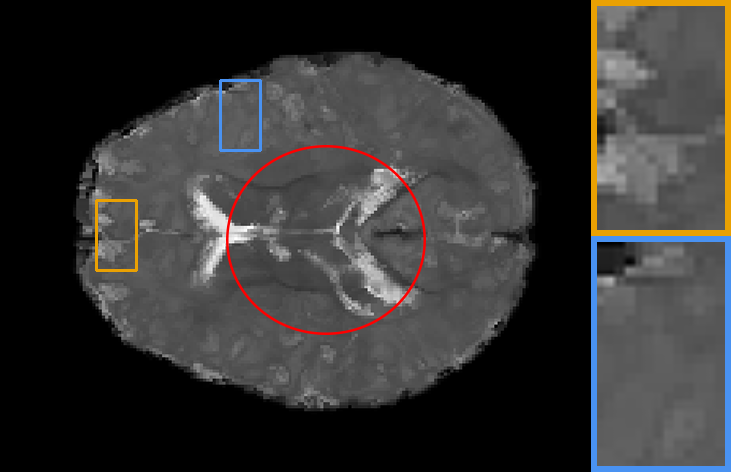

| Brain T1-to-T1 | Brain T2-to-T2 | Knee T1-to-T1 | Brain T2-to-T1 |

IV-C2 Automatic learning across registration tasks

To explore the influence of model weights, architectures, and training objectives in registration performance and verify the benefit from adaptive feature extraction cell, task-aware deformation estimation cell design, and scenario-oriented training objectives, we made groups of contrast experiments, covering diverse registration scenarios. Specifically, we first train a registration model on PPMI brain T1 MR image-to-atlas registration tasks, then take the model as initialization to adopt our auto-search strategy to register images of other different scenarios. The scenarios cover registration on another ADNI dataset, Brain T1-to-T1, Brain T2-to-T2, Knee T1-to-T1 and Brain T2-to-T1 setups.

In Table. II, we directly apply the model (with , , and ) on the PPMI dataset to other scenarios, corresponding to the 1st column result, showing poor performance. Whereas performances of re-trained models (with task-specific model weight ) on these tasks correspond to the 2nd column. We also demonstrate the performance of searched networks with auto-learned feature cells , deformation cells , and training objectives , corresponding to the 3rd to 5th columns. To fully capture the benefit of the proposed technique, we further report the increase in registration accuracy for cases where all hyperparameters are searched in the last column. We can observe that, firstly, retraining the model for different alignment tasks will result in better performance. Secondly, searched tailored architecture and training objectives largely improve numerical results, which means automatic learning combining training objectives, architectures and hyperparameters can achieves excellent alignment performance in different alignment scenarios.

Also, the models on the diagonal with a blue background perform second best which can be seen from Table. II, providing meaningful indications and conclusions. Firstly, when transferring to another dataset or image contrast, feature extraction plays a dominant role in model performance. Secondly, whereas transferring to another anatomical structure such as the knee data, regulating the deformation estimation section has a more significant impact on the performance of the model. Lastly, adjusting the training objective plays a more important role in the performance of a registration network when transferring to multi-modal datasets.